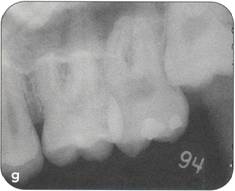

Fi 545e45f g 5-4f Extracted second molar, which will be discarded. Fi 545e45f g Extracted donor tooth. The amount of periodontalligament is adequate. Transplantation was performed 6 weeks after extraction of the tooth from the recipient site. Fi 545e45f g 5-4h View of the donor site and preparation of the recipient site. |

Fi 545e45f g 5-4i After the gingival flap has been sutured and the donor tooth has been splinted. The distal aspect of the donor tooth is closed as tightly as possible. Fi 545e45f g 5-4j After transplantation. Fi 545e45f g 5-4k Two weeks after trans plantation |

Fi 545e45f g 5-41 Six weeks after transplantation. The root canals have been cleaned, shaped, and filled with calcium hydroxide. Fi 545e45f g 5-4m Three months after transplantation. The radiograph was taken after removing the splint. Fi 545e45f g 5-4n Seven months after transplantation. |